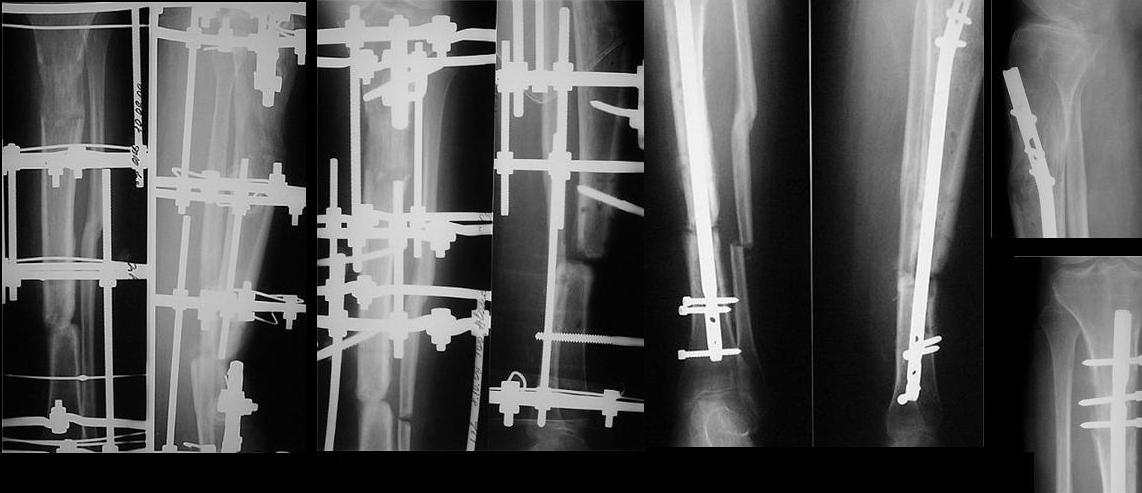

31.10.09 г. сделан первый этап операции: остеосинтез спице-стержневым

аппаратом 7.11.09 г. выполнен второй этап - БИОС с рассверливанием

канала, операция прошла без ожидаемых трудностей, открывать зону

ложного сустава не пришлось. Прошу сделать замечания. Виктор.